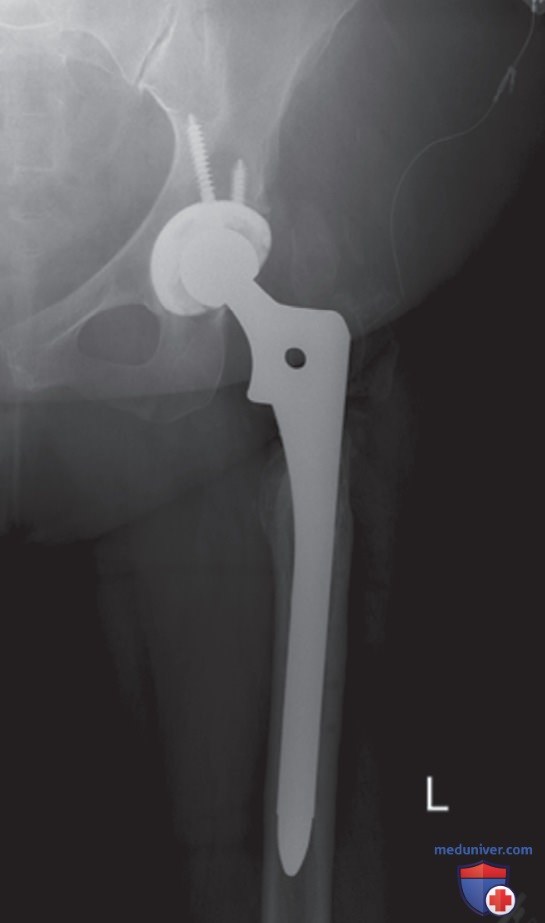

Рисунок 5. Рентгеноконтрастные материалы, например металлические листы или мешочки с песком, содержат большее количество атомов, чем кости и мягкие ткани. Если активированная ионизационная камера располагается под рентгеноконтрастным предметом, то работа АКЭ в попытке адекватно экспонировать этот предмет приведет к избыточной экспозиции анатомических структур. В результате ухудшится контрастное разрешение и может возникнуть сатурация.

• Никогда не используйте АКЭ, если над активированной камерой (камерами) располагаются рентгеноконтрастные металлоконструкции и протезы. В таких случаях пользуйтесь ручным режимом (рис. 5)

• Во избежание получения внешних артефактов убедитесь, что над активированной камерой (камерами) отсутствуют рентгеноконтрастные предметы, например свинцовые листы и мешочки с песком